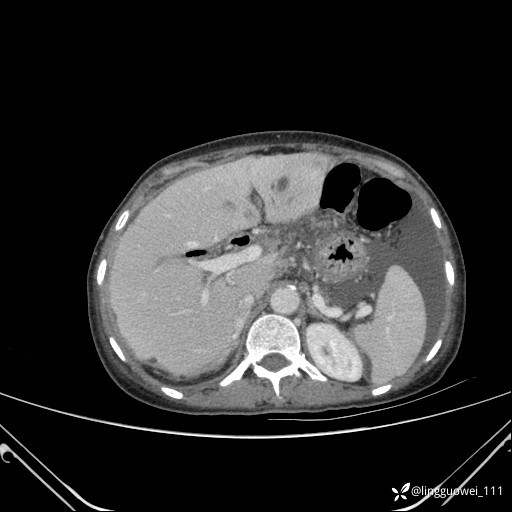

病例女,65岁,门诊行胃肠镜检查后,说腹胀入院检查,CT能发现病因吗?已公布结果

患者性别:女

患者年龄:65岁

主诉:门诊行胃肠镜检查后,诉腹胀,入院检查,肝有病变吗?腹膜及腹腔的表现有特征性吗?

增强动脉期: